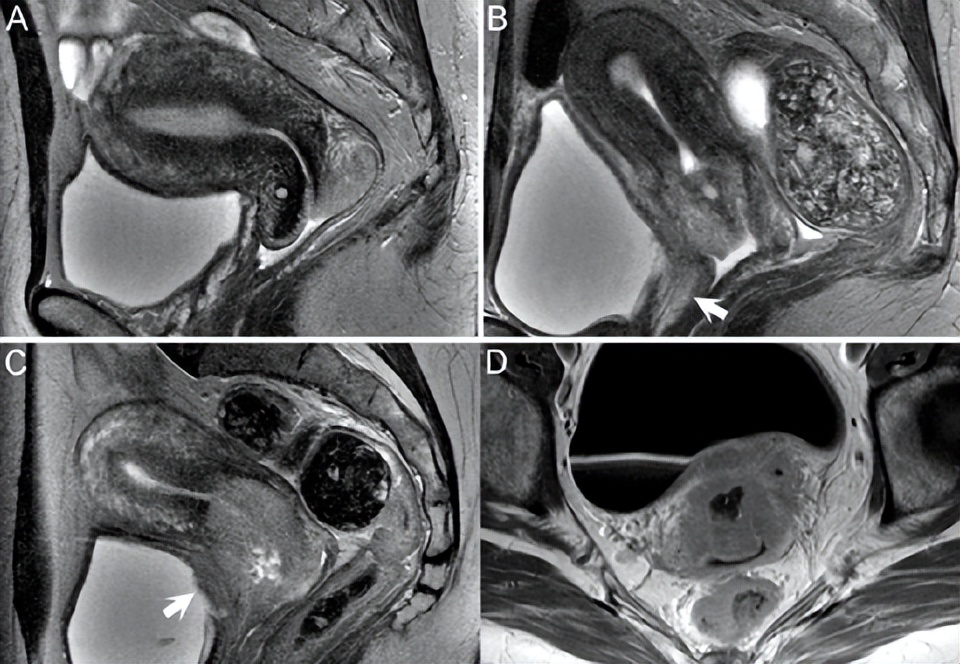

▲ 图75.2

宫颈癌的分期首选MRI。不能检测到0期或原位癌,而1A期病变(在T2WI上显示为高信号,与低信号宫颈间质相对照)被明确视为局限于宫颈的微浸润性病变。如图75.2A所示,1B期病变深度大于5 mm或横向范围大于7 mm。(A)矢状位T2WI示完整的低信号颈前唇基质,仅被高信号加德纳囊肿中断。后唇的低信号被高信号肿块取代,无低信号基质包膜。图中的75.2B为2A期病变,累及阴道前壁上部三分之二,但不累及下部三分之一(即3A期)(白色箭头)。T2WI高信号反映的浸润构成2B期病变,而盆腔侧壁浸润表示3B期病变。对比增强序列不能改善宫旁浸润的诊断。然而,使层方向垂直于宫颈通道的长轴对于准确评估非常重要。

放化疗性水肿可伪装为这些结构的肿瘤受累,其在T2WI上呈高信号。直肠远处转移或侵犯以及膀胱粘膜受累构成4期病变。后一种情况如图75.2C的矢状位T2WI所示,伴不均匀高信号的宫颈肿瘤浸润阴道上三分之一处并中断低信号膀胱壁(白色箭头)。图75.2D的轴向CE T1WI上也有类似表现,其中不规则增强的肿瘤突入膀胱壁。宫颈癌的对比增强是多样的,但CE T1WI可能极大地有助于评估浸润性宫颈癌的程度。